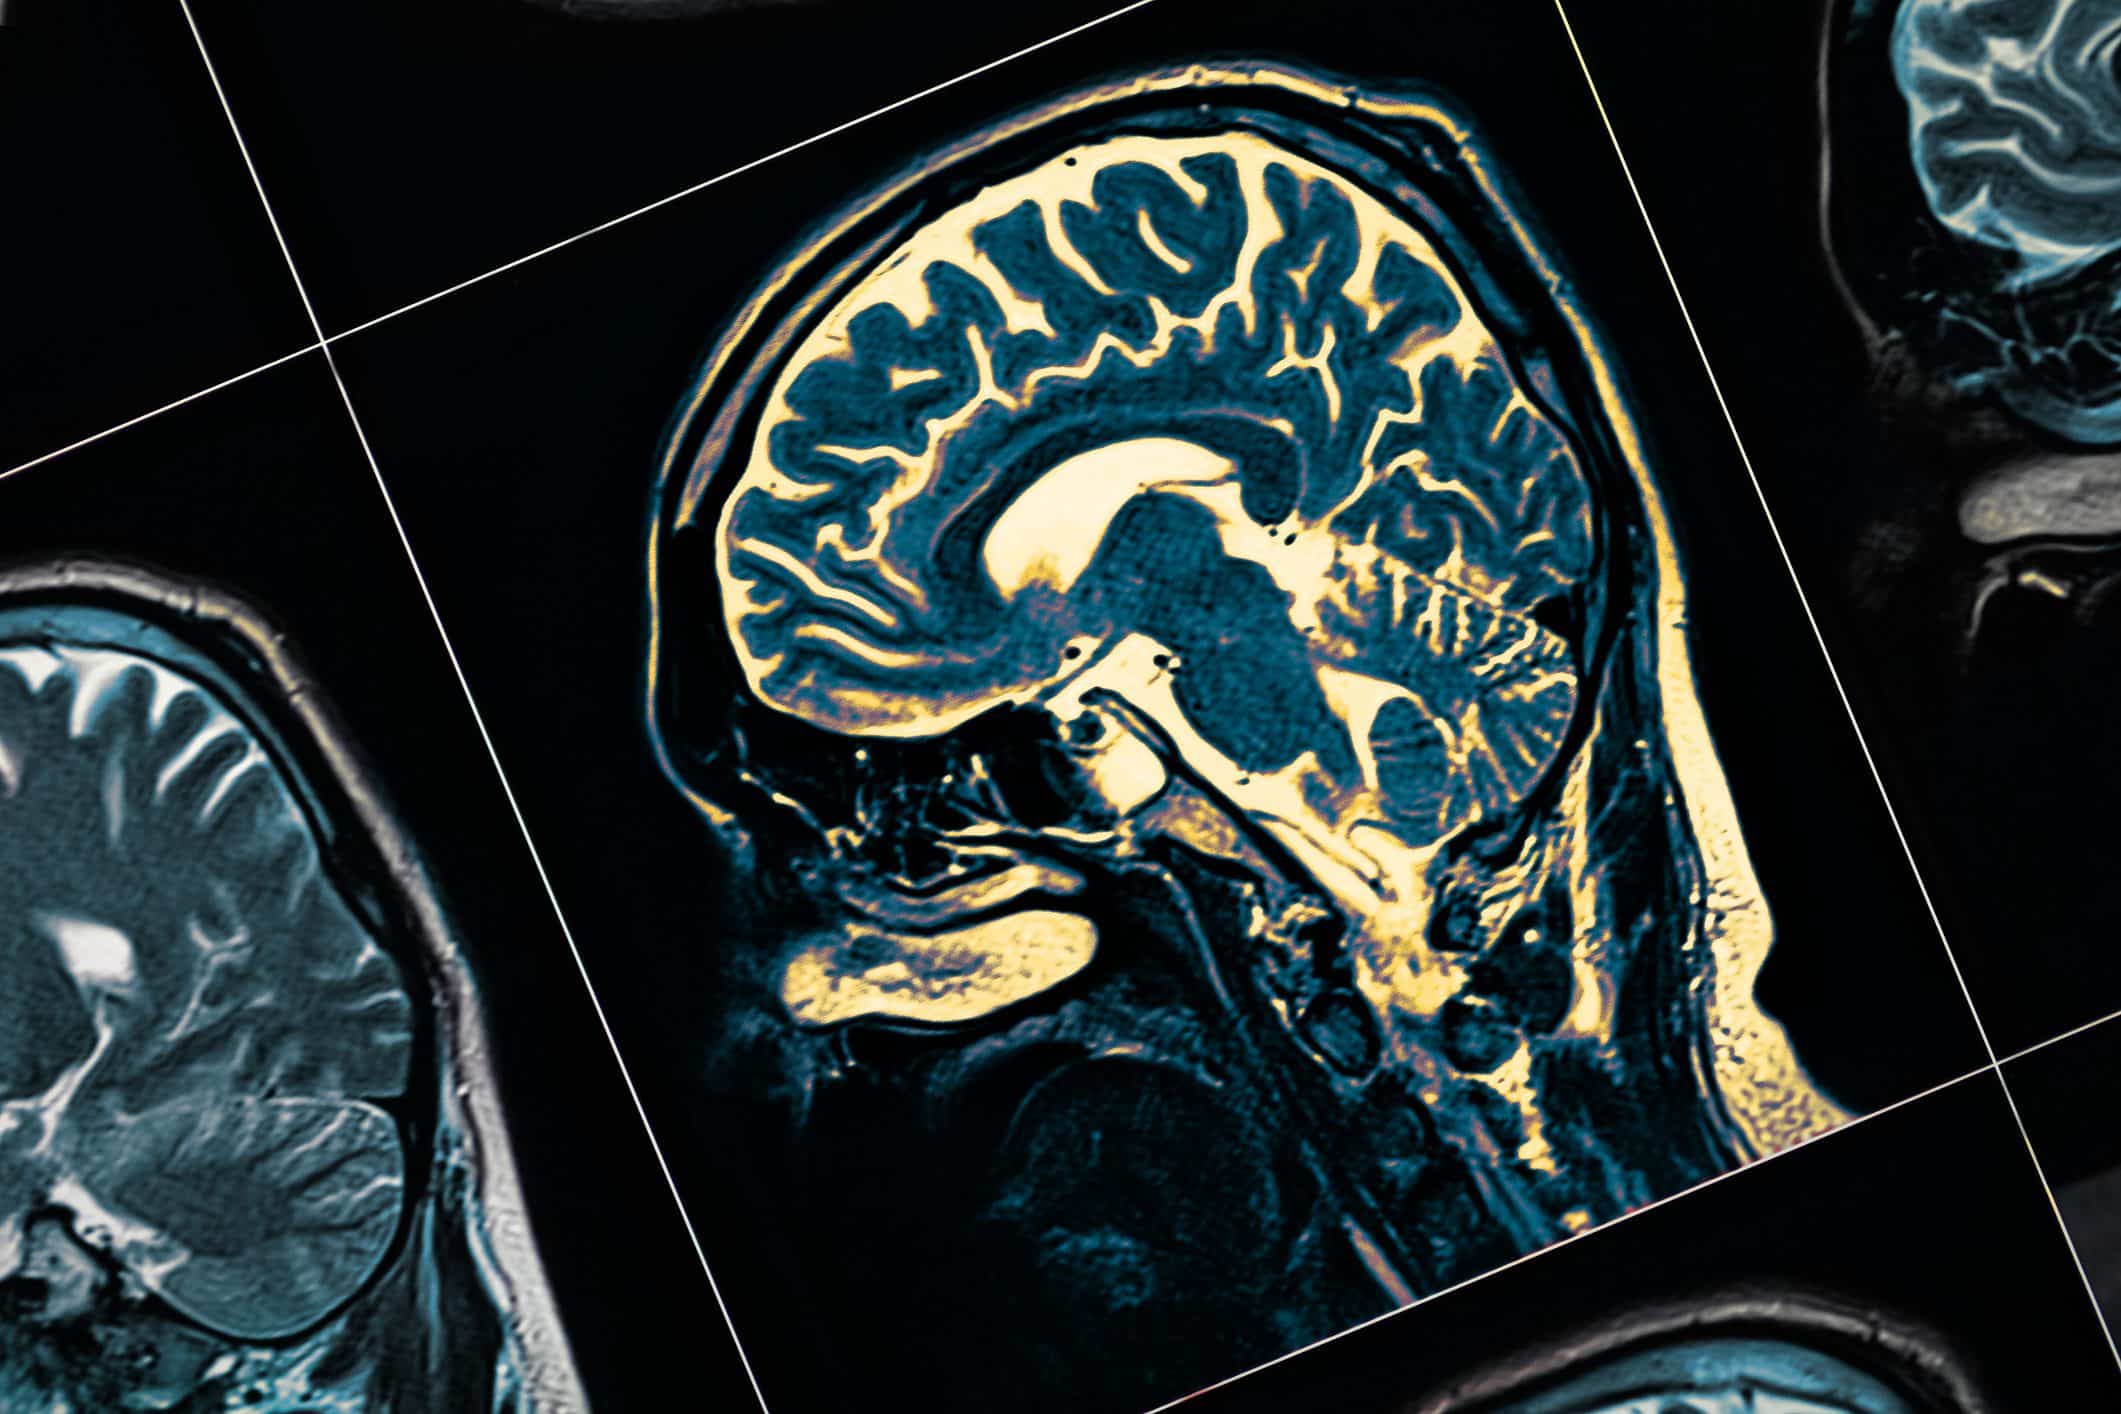

Parkinson’s disease is a condition that affects the brain and the nervous system. Over time, it changes how a person moves and functions. This progressive movement disorder develops slowly, with symptoms changing as the years go by.

Inside the brain, there are special nerve cells that produce a chemical called dopamine, which acts as a messenger sending signals to the parts of your brain that control movement and coordination. When a person has Parkinson’s disease, these nerve cells gradually stop working and die. As dopamine levels drop, the brain cannot send proper signals to the muscles, leading to movement problems.

If you notice any of the above symptoms, your first step should be to see your GP or a Specialist. While there’s no single blood test or brain scan that can definitively diagnose Parkinson’s disease, we’ll carefully evaluate your health.